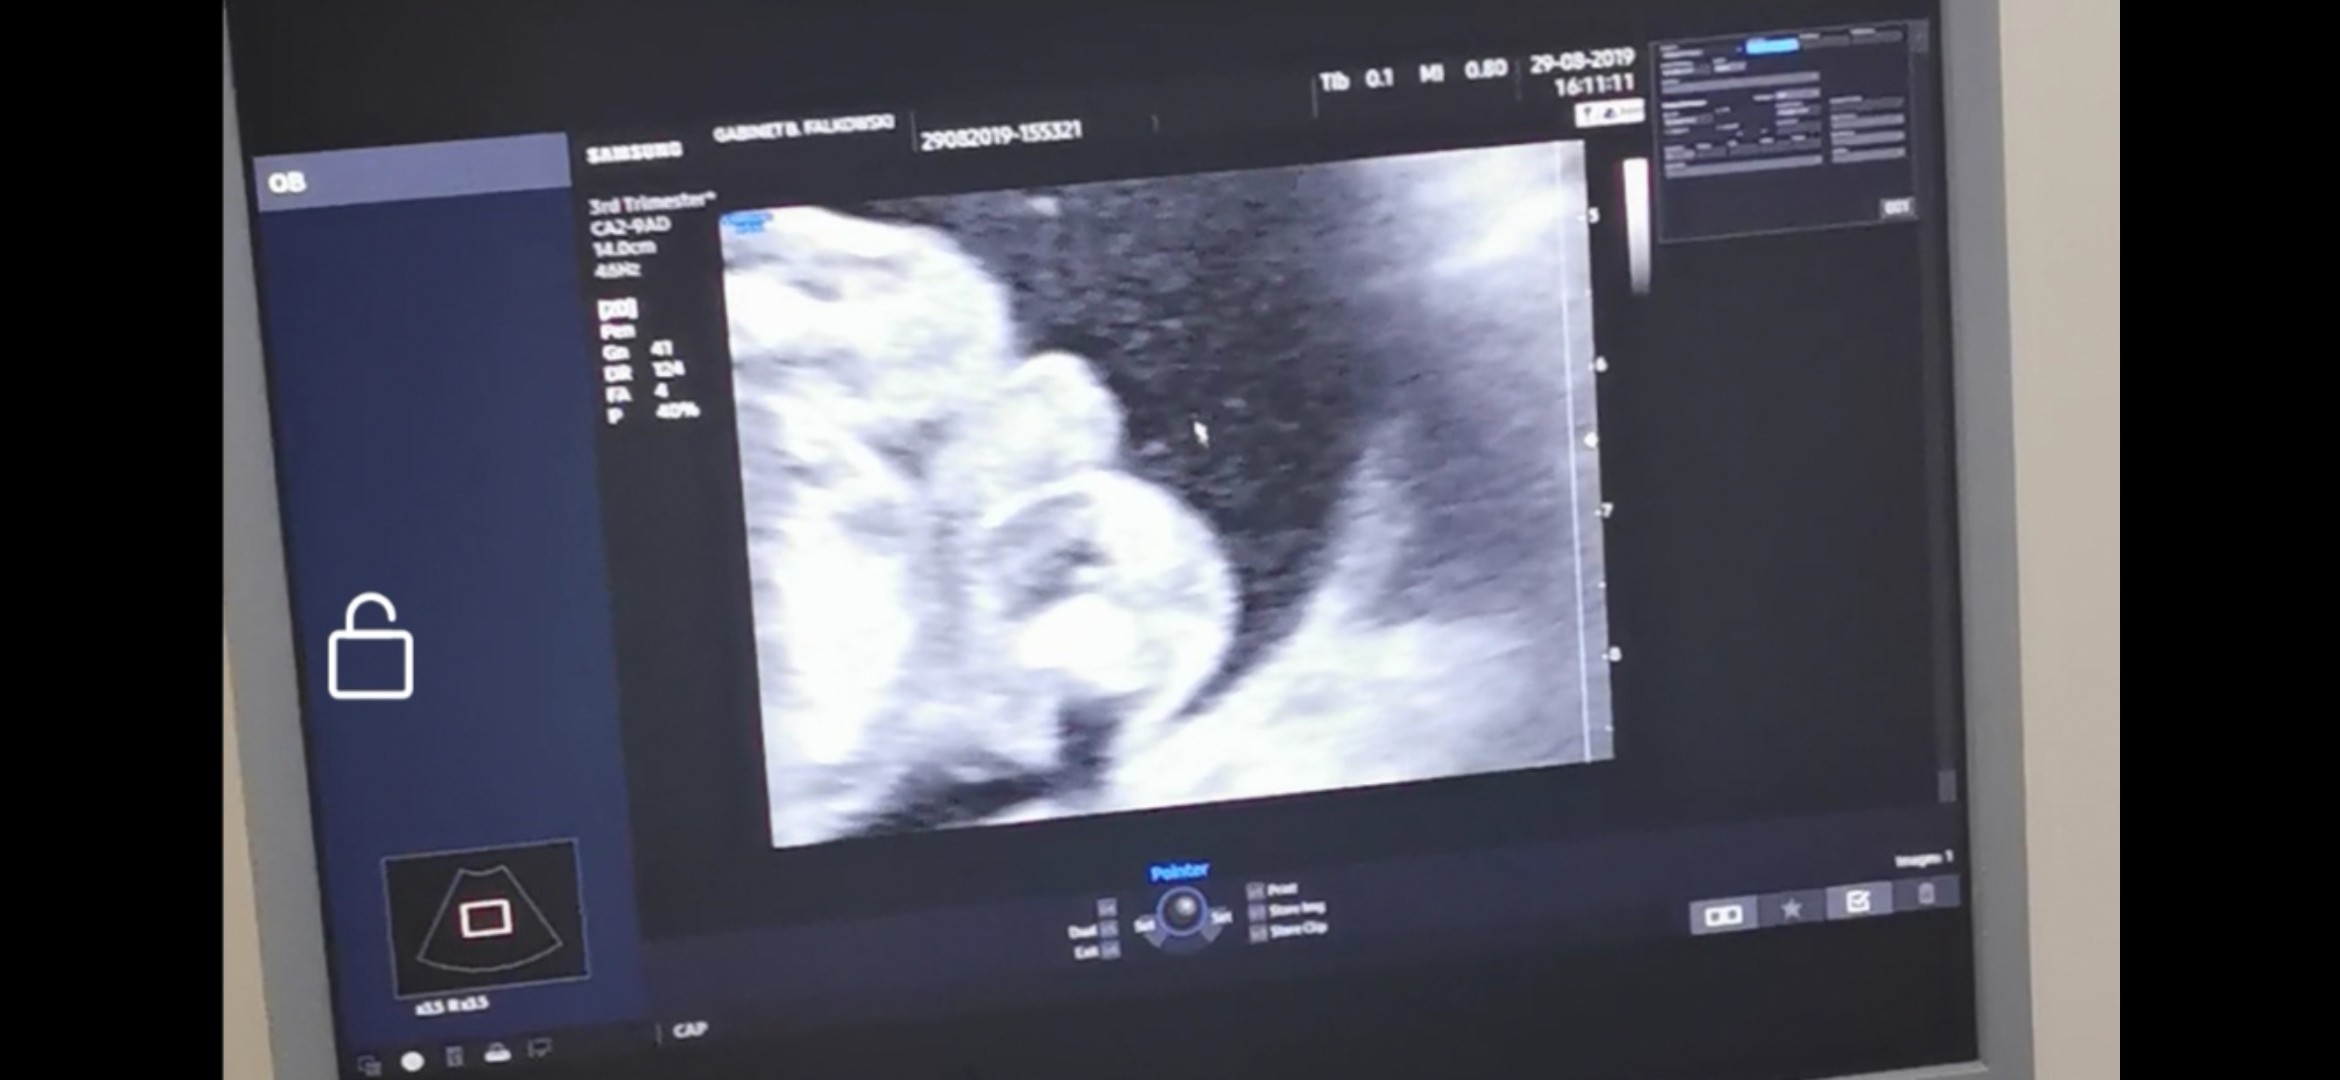

Usg chłopiec czy dziewczynka?